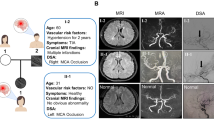

Moyamoya disease is a chronic occlusive cerebrovascular disease, which is characterized by progressive stenosis or occlusion of the terminal internal carotid artery (ICA) and its proximal branches, accompanied by the formation of abnormal collateral vessels [1, 2]. The incidence of Moyamoya disease has obvious geographical differences, which is more common in Japan, China, Korea, and southeastern Asian countries [3]. The main clinical manifestation of Moyamoya disease is unpredictable hemorrhagic or ischemic stroke, which causes high mortality and disability rates [4]. The pathogenesis of Moyamoya disease has not been elucidated, which may involve angiogenesis, genetic factors, and immune and inflammatory responses [4, 5]. Recently, some reports [6, 7] have described impaired cytoskeletal regulation, and fibroplasia of smooth muscle cells may be the potential etiology.